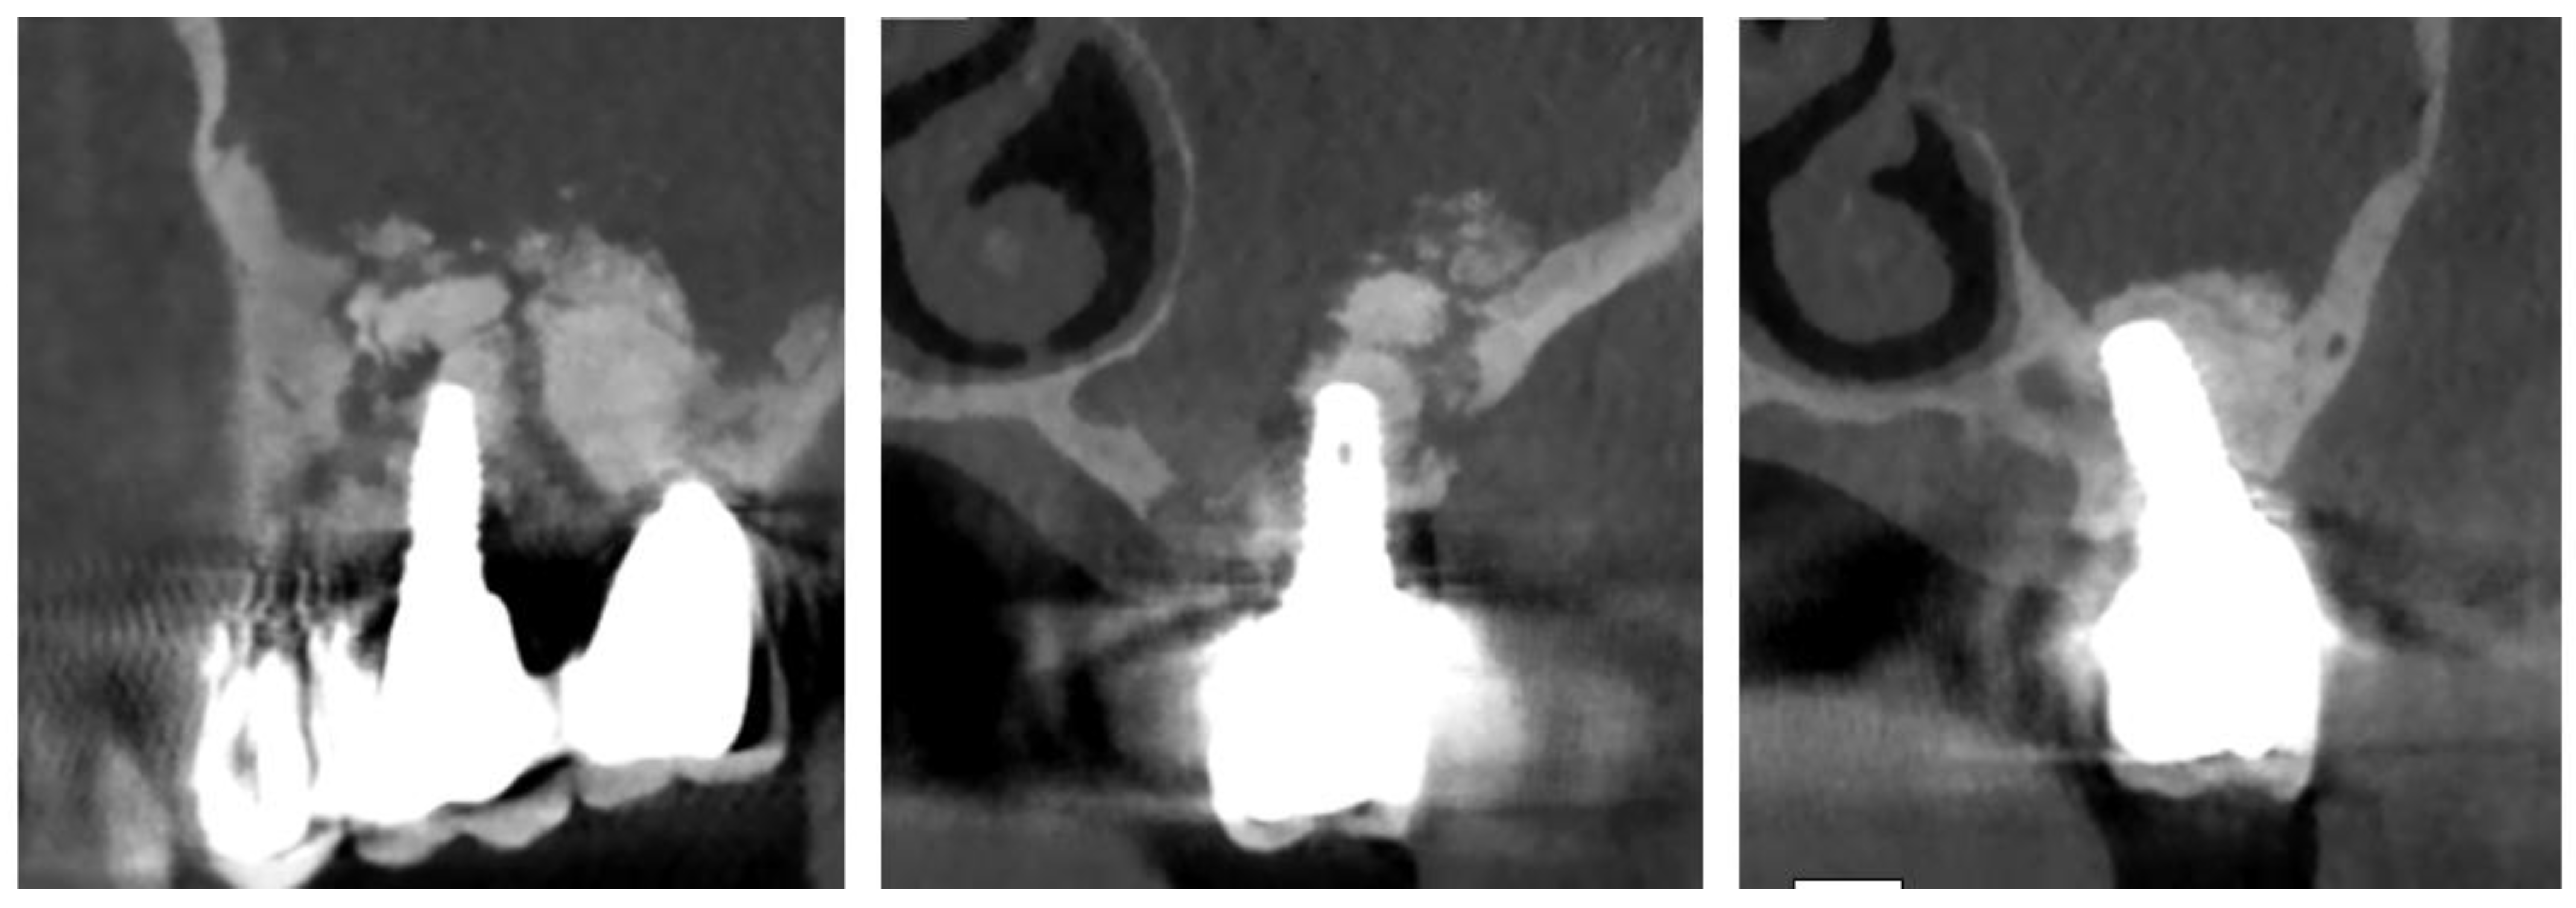

Figure 3. Full thickness flap elevation.

Figure 4. Osteotomy with piezoelectric device.

Figure 5. Osteotomy completed polipoid tissue in the maxillary sinus.